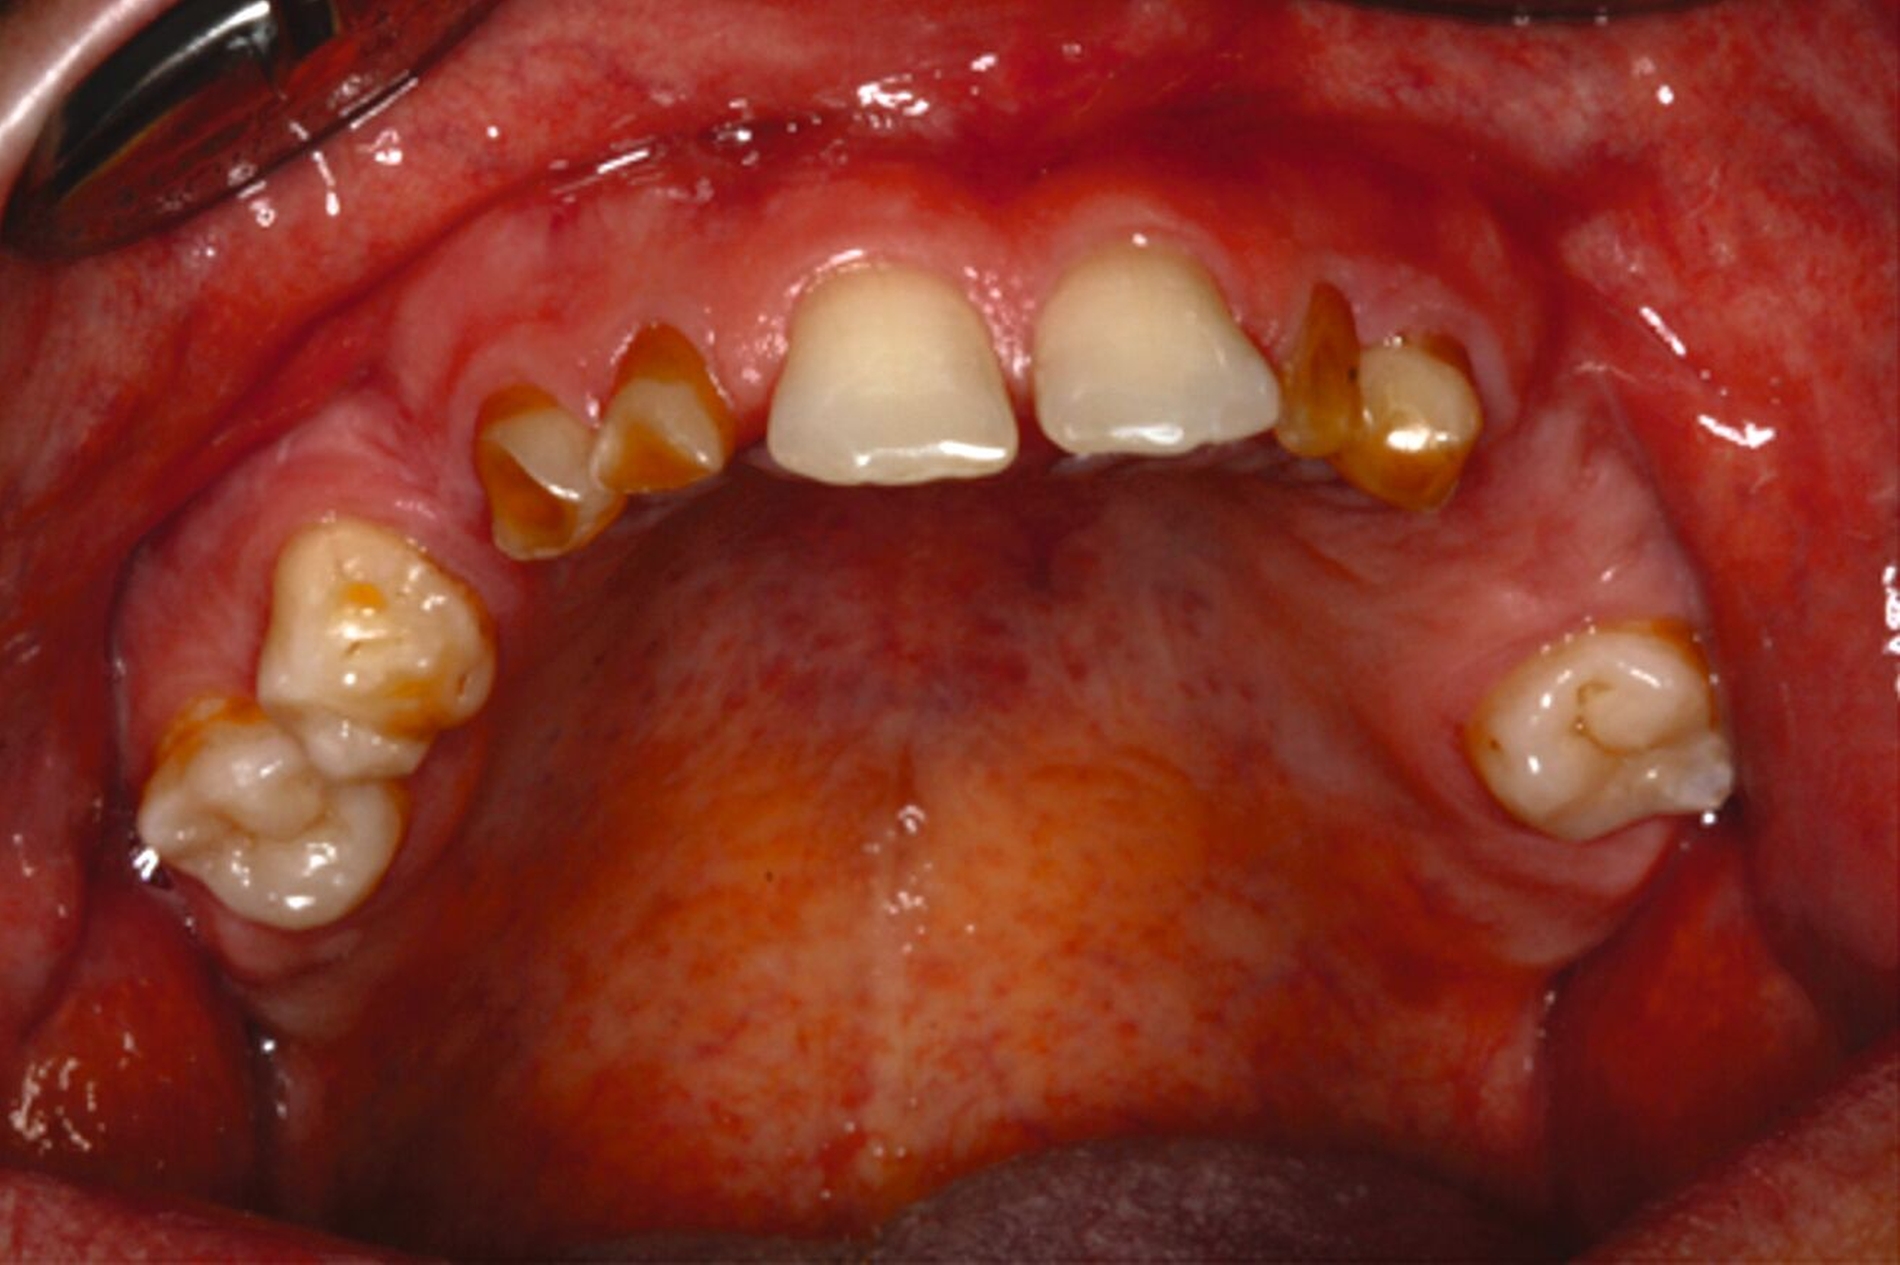

Eine mögliche und indizierte Umstellungsosteotomie wurde vom Patienten abgelehnt. Da seitens des Patienten eine Kopfbissstellung möglich war, wurde eine Bissumstellung und -hebung mit nur noch geringgradigem Vorbiss und anschließender Zahnimplantation in Erwägung gezogen. Begonnen wurde mit einer temporären Schienentherapie zur Neuorientierung der Bisslage (Abbildung 3). Da der Patient die angepasste Bisshebung tolerierte, wurde diese nach Entfernung der persistierenden Milchzähne 55, 53, 52, 62 und 83 temporär mittels einer Valplastprothese (Abbildung 4) als Interimsersatz im Oberkiefer gesichert.

Im Oberkiefer: Implantationen zur Pfeilervermehrung und Teleskopversorgung, alternativ festsitzende Kronen-Brückenversorgungen. Eine Teleskopversorgung allein auf den restlichen natürlichen Zähnen wäre aufgrund der vertikalen Distanz nach erforderlicher Bisshebung nicht möglich gewesen.

Kronenverlängerungen und Überkronungen der teilretinierten Zähne 16 und 26.